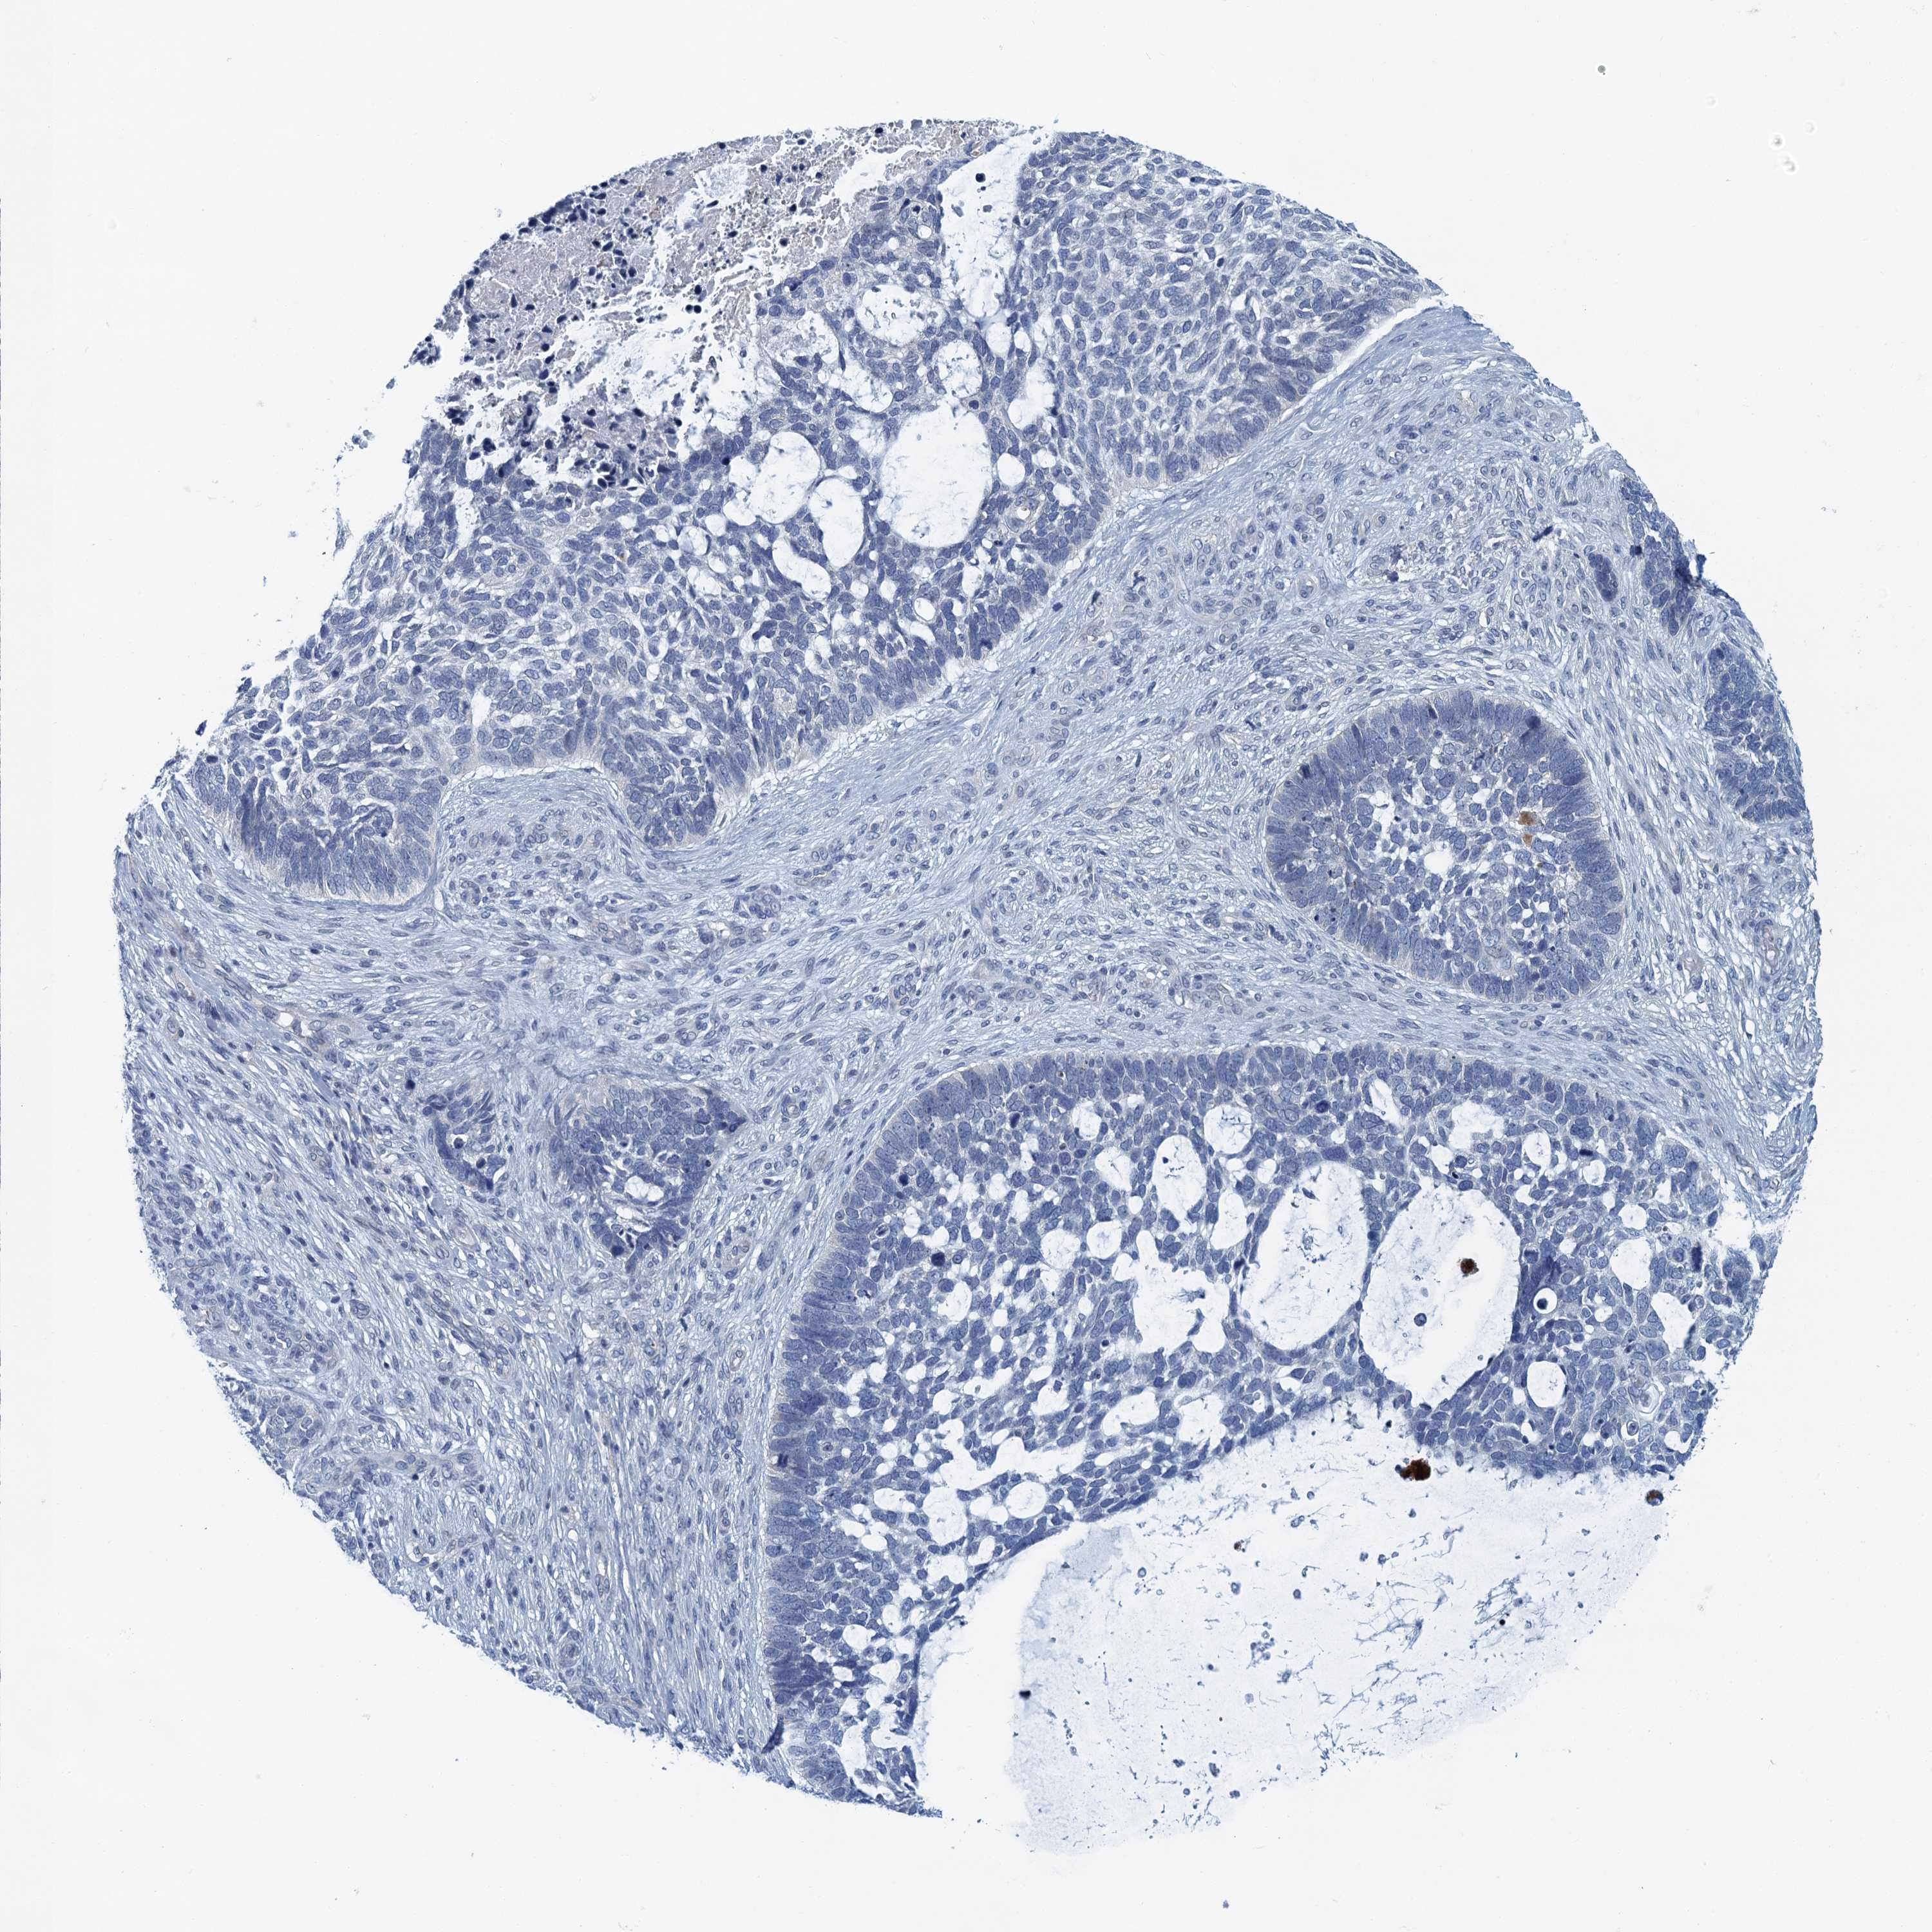

Basal cell and squamous cell cancer

SKIN CANCER - Protein expressioni

A mouse-over function shows sample information and annotation data. Click on an image to view it in a full screen mode. Samples can be filtered based on level of antibody staining by selecting one or several of the following categories: high, medium, low and not detected. The assay and annotation is described here.

Each image is clickable and will lead to virtual microscopy that enables deeper exploration of all samples and also displays staining intensity scores, fraction scores and subcellular localization as well as patient and tissue information for each sample.

Antibody HPA039490

Antibody HPA040772

Staining

High

Medium

Low

Not detected

Intensity

Strong

Moderate

Weak

Negative

Quantity

>75%

75%-25%

<25%

None

Location

Nuclear

Cytoplasmic/membranous

Cytoplasmic/membranous,nuclear

Basal cell carcinoma

Squamous cell carcinoma, NOS

Squamous cell carcinoma, metastatic, NOS